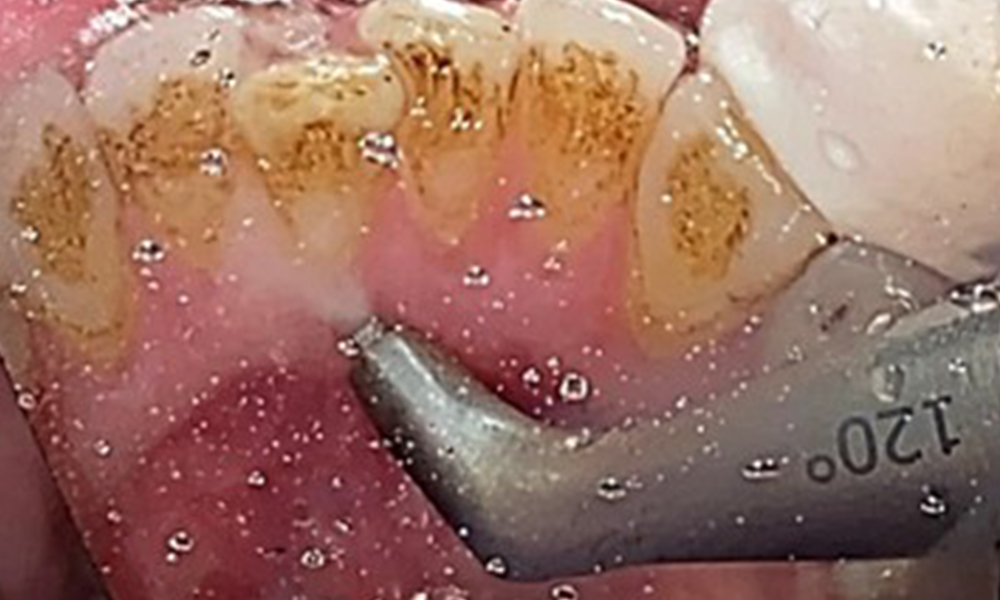

Aufgrund des guten allgemeinmedizinischen Zustandes ist der aus der Mundgesundheit ermittelte Bedarf maßgebend für die Behandlung. Die regelmäßige Erhebung der Sondierungstiefen ist unabdingbar. Die gingivale Blutung ist bei Rauchern herabgesetzt, weswegen die klinische

Diagnose einer Parodontitis nur durch Sondierung möglich ist (Abb. 7). Die ausschließliche Erhebung von Blutungsindizes verdecken unter Umständen das Bild einer bestehenden Parodontitis oder Gingivitis. (5)

Taschensondierung (BOP) mit Darstellung der Rg. 36 lingual

Abb. 7 Taschensondierung (BOP) mit Darstellung der Rg. 36 lingual, © Dr. R. Krapf

Ziel ist es durch supra- und subgingivale Biofilmentfernung das Erkrankungsrisiko zu kontrollieren. Die Wahl der Instrumente erfolgt

bedarfsgerecht. Zunächst sind Zahnstein und ggf. Konkremente mit Ultraschall und / oder Handinstrumenten zu entfernen (Abb. 10).

Anwendung eines piezobetriebenen Ultraschallgerätes in Rg 36

Abb. 10 Anwendung eines piezobetriebenen Ultraschallgerätes in Rg 36 lingual (hier Proxeo Ultra, Firma W&H), © Dr. R. Krapf